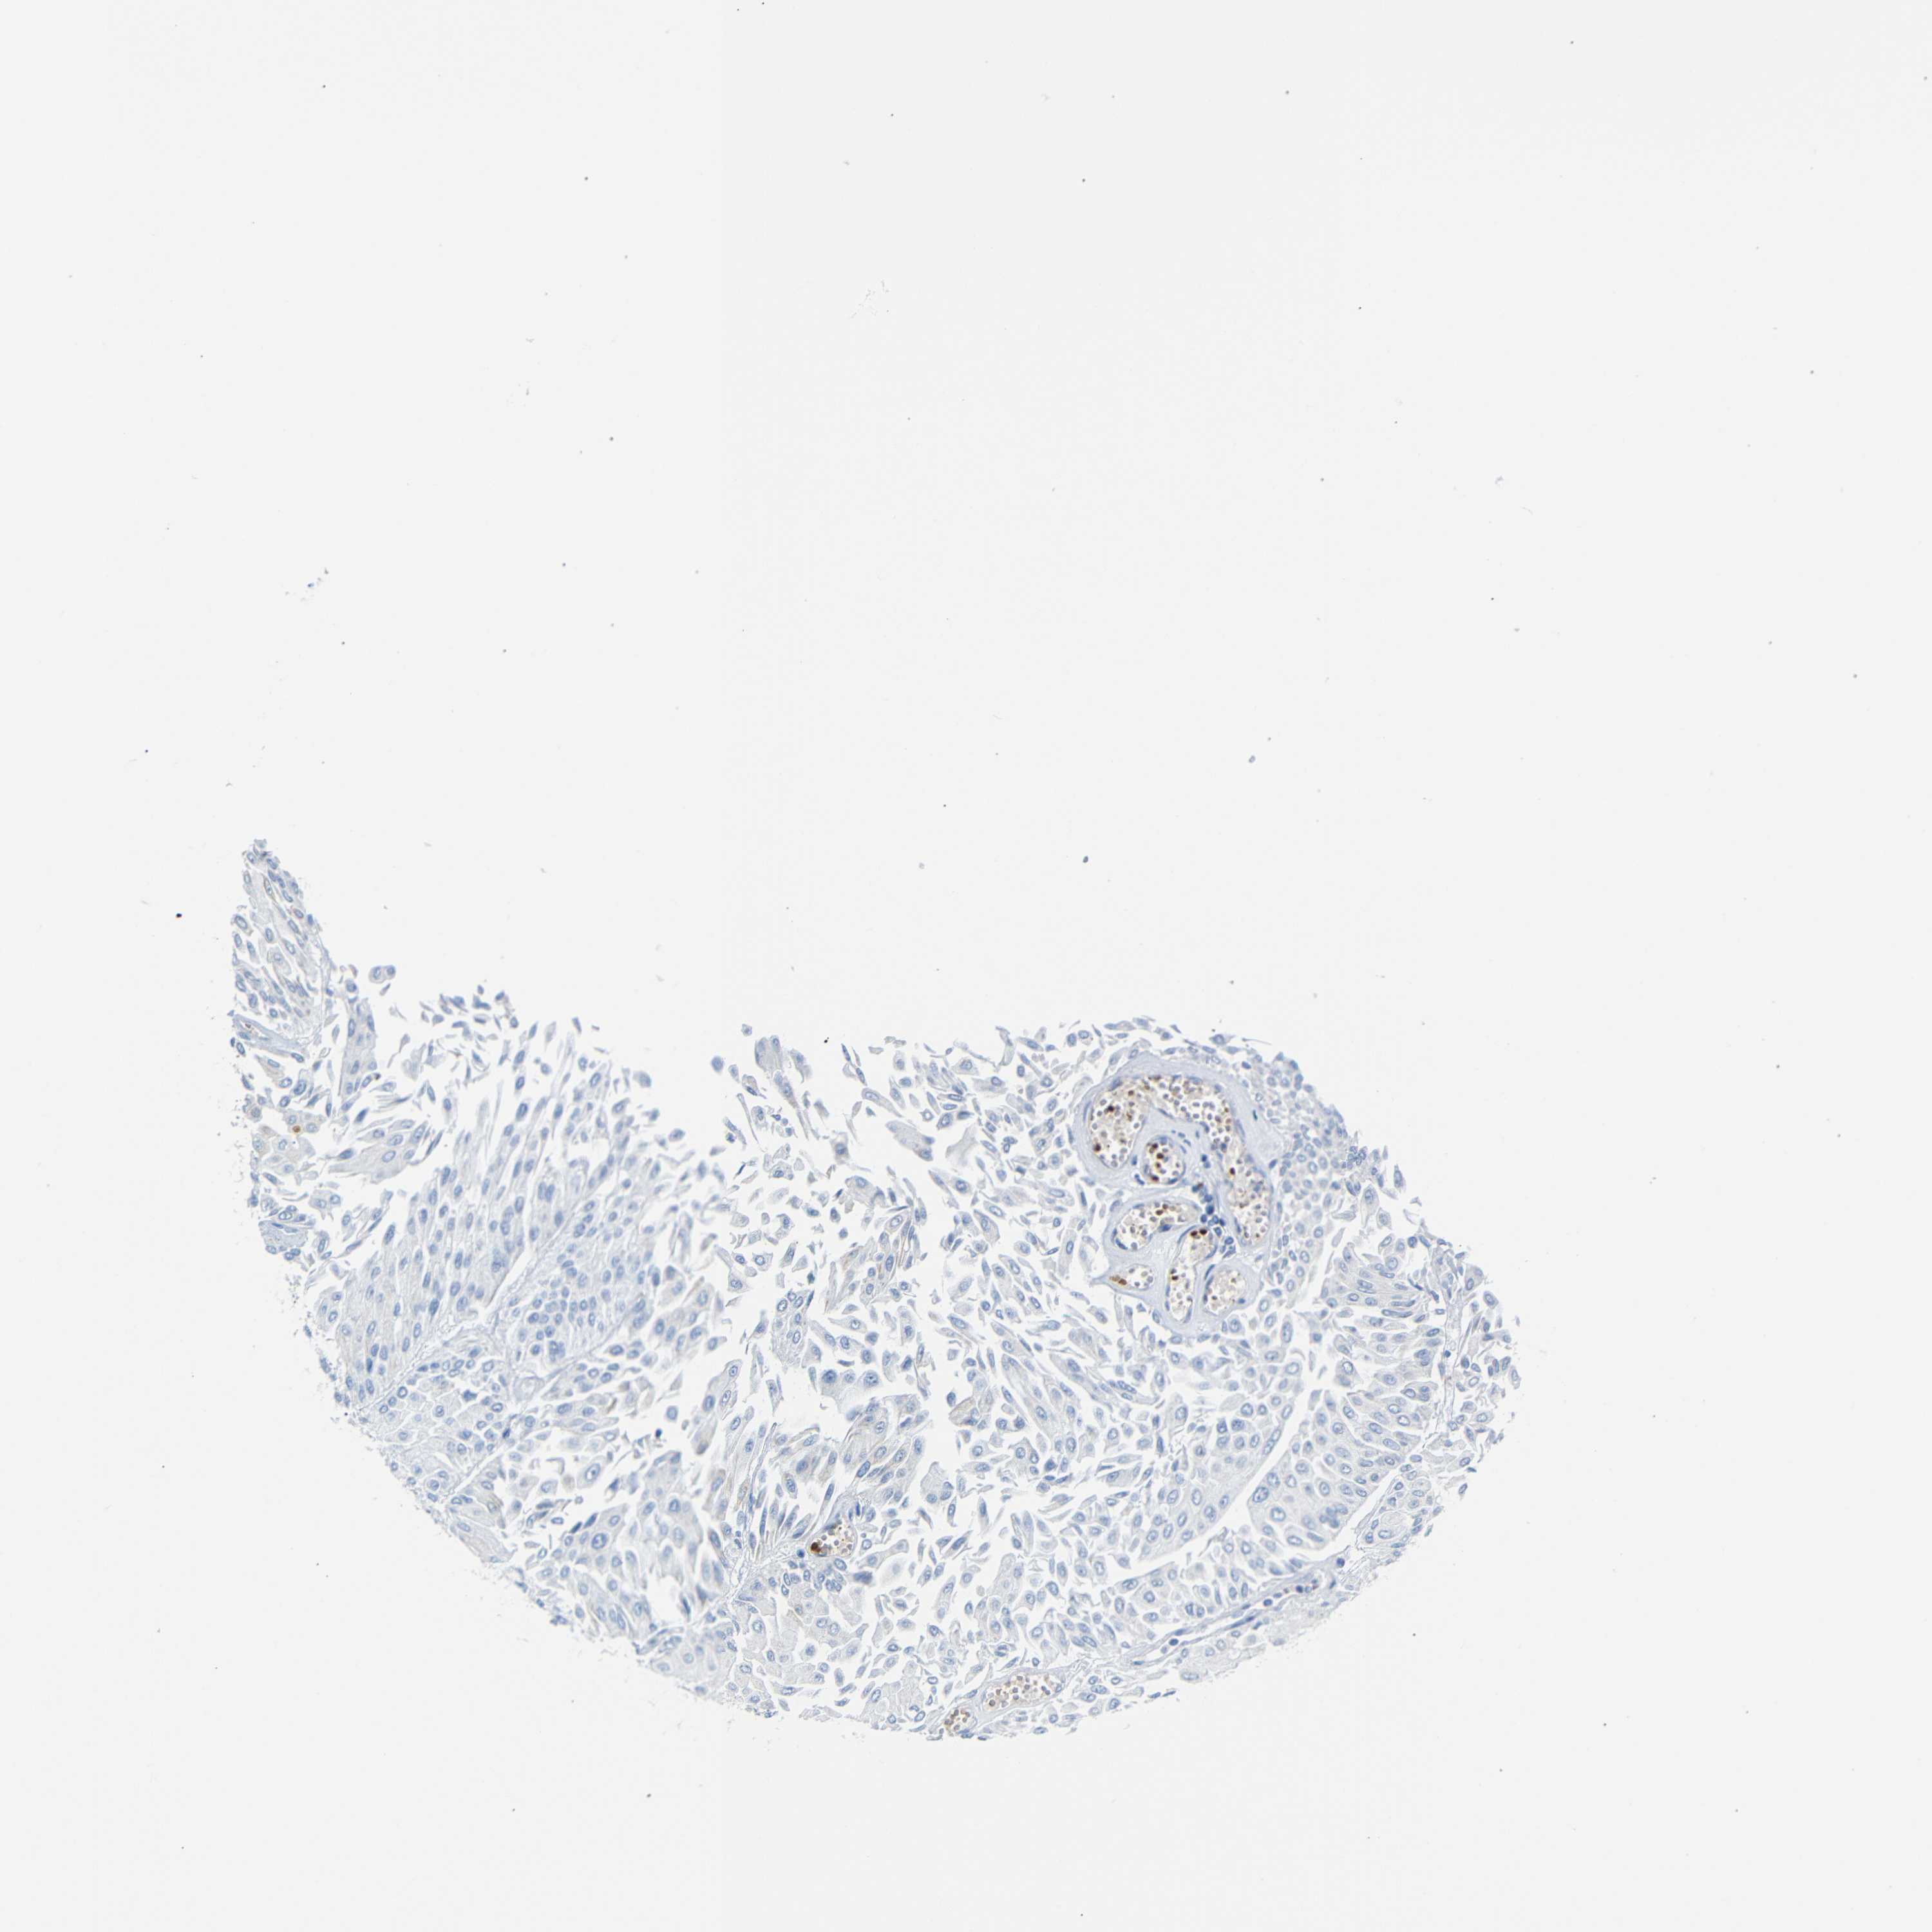

UROTHELIAL CANCER - Protein expressioni

A mouse-over function shows sample information and annotation data. Click on an image to view it in a full screen mode. Samples can be filtered based on level of antibody staining by selecting one or several of the following categories: high, medium, low and not detected. The assay and annotation is described here.

Note that samples used for immunohistochemistry by the Human Protein Atlas do not correspond to samples in the TCGA dataset.

Antibody stainingi

Antibody staining in the annotated cell types in the current human tissue is reported as not detected, low, medium, or high, based on conventional immunohistochemistry profiling in selected tissues. This score is based on the combination of the staining intensity and fraction of stained cells.

Each image is clickable and will lead to virtual microscopy that enables deeper exploration of all samples and also displays staining intensity scores, fraction scores and subcellular localization as well as patient and tissue information for each sample.

Antibody HPA011423

Staining

High

Medium

Low

Not detected

Intensity

Strong

Moderate

Weak

Negative

Quantity

>75%

75%-25%

<25%

None

Location

Nuclear

Cytoplasmic/membranous

Cytoplasmic/membranous,nuclear

Urothelial carcinoma, Low grade

Urothelial carcinoma, High grade